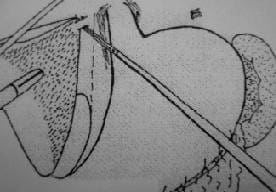

Para la cirugía se adoptó la posición francesa, con las extremidades inferiores separadas y en posición de Trendelemburg invertida. El cirujano se ubicó entre las extremidades inferiores, el primer ayudante a la derecha y el segundo ayudante (manejo de la cámara) al lado izquierdo del paciente (figura 3). Para el monitoreo constante de la presión venosa central, la cual se mantuvo por debajo de 5 cm de agua durante todo el procedimiento, y para suministrar cristaloides o productos sanguíneos, se obtuvo un acceso venoso central (subclavio derecho).

FIGURA 3. Configuración del equipo de trabajo. El cirujano se localiza entre las piernas del paciente. Los asistentes se ubican a los lados del paciente. El monitor se coloca a la cabecera del paciente.